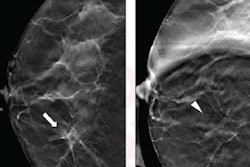

Ultrasound should be the first line for diagnostic workup of noncalcified masses recalled from digital breast tomosynthesis (DBT) exams, according to research published December 15 in the American Journal of Roentgenology.

A team led by Dr. Jessica Porembka from the University of Texas Southwestern Medical Center found that ultrasound by itself is effective in diagnostically evaluating noncalcified masses recalled on screening DBT.

DBT has seen increased use in the U.S. over the past 10 years following clearance of the first systems. The study authors said this is due to the technology's increased cancer detection rate and lower recall rate compared with conventional digital mammography.